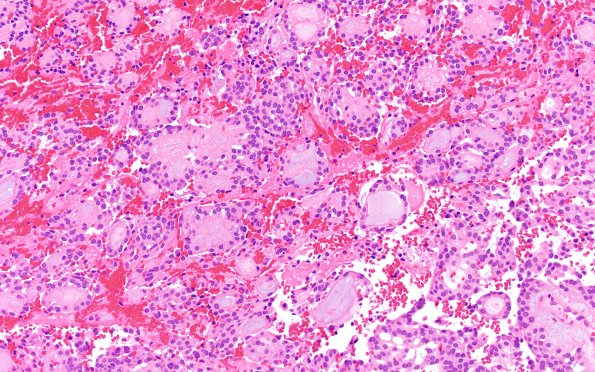

Washington University Experience | NEOPLASMS (GLIAL) | Ependymoma, myxopapillary | 22A2 MPE (Case 22) H&E 20X 1

H&E-stained sections show a well-circumscribed neoplasm composed of mildly pleomorphic cells with eosinophilic cytoplasm and slightly distinct borders which are organized around papillae with fibrovascular cores. Most of these papillae envelop nests of myxoid material. Mitoses are present (up to 2/10 HPF) but not abundant. (H&E)